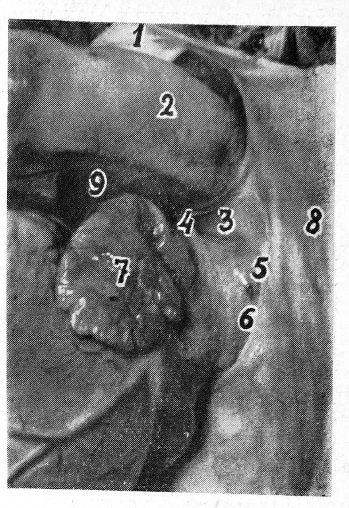

Промежуток ограничен слева восходящей аортой, справа верхней полой веной, сверху листком перикарда, переходящим на дугу аорты, снизу верхней стенкой правого предсердия (рис. 2). Длина промежутка 6—7 см, ширина 2,0—2,5 см. В этом промежутке в среднем отделе хорошо обнаруживается цилиндрическая выпуклость, идущая в поперечном направлении. Она образована правой легочной артерией. Выше и ниже ее располагаются два углубления — верхний и нижний перикардиальный карманы.

Верхний перикардиальный карман представляет собой более или менее выраженное углубление овальной формы. Оно соответствует правому трахеобронхиальному углу и правой части дистального отдела трахеи. Между перикардом и трахеобронхиальным углом расположен слой клетчатки толщиной 0,5—1,5 см. Цилиндрическая выпуклость повторяет контур правой легочной артерии, расположенной за задним листком перикарда. Длина этого отдела артерии 2,0—2,5 см, диаметр 1,5—1,8 см. Правая легочная артерия соответствует центральному отделу правого главного бронха.

Ниже контура правой легочной артерии располагается второе, несколько меньшее углубление — нижний перикардиальный карман, в него выходит правое отверстие поперечного синуса сердца. Нижний перикардиальный карман соответствует бифуркации трахеи.

Рис. 2. Средний сердечно-перикардиальный промежуток (аортокавальный):

1 — восходящая аорта; 2 — верхняя полая вена; 3 — правое предсердие и его ушко; 4 — верхняя стенка перикарда; 5 — контур правой легочной артерии; 6 — верхний перикардиальный карман; 7 — нижний перикардиальный карман и правый вход в поперечный синус.